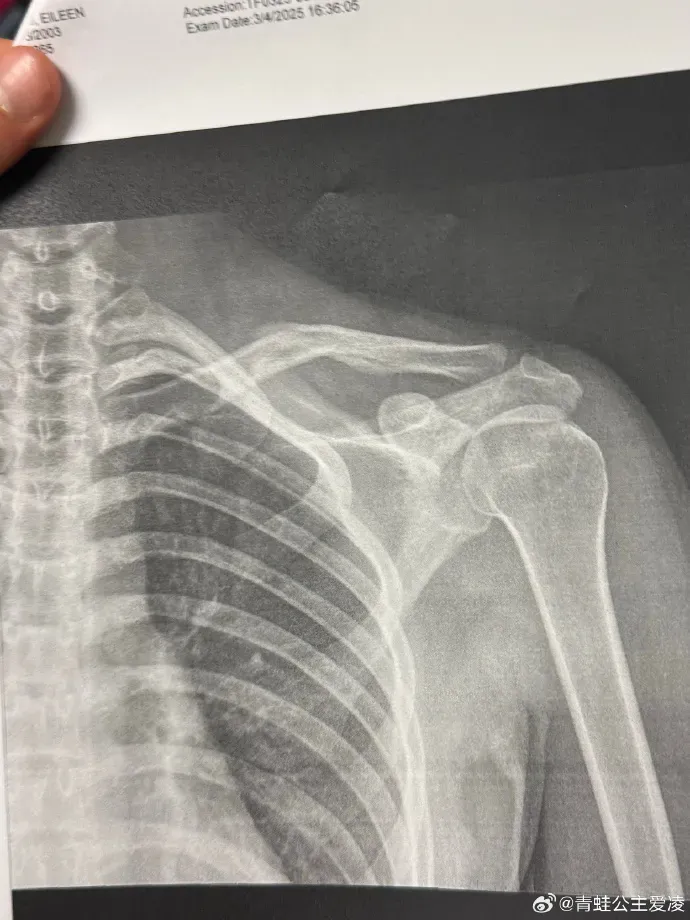

本年3月9日,谷爱凌在酬酢媒体晒出肩部骨折的X光像片,并配上一个心碎的形势,随后关联话题登上热搜。